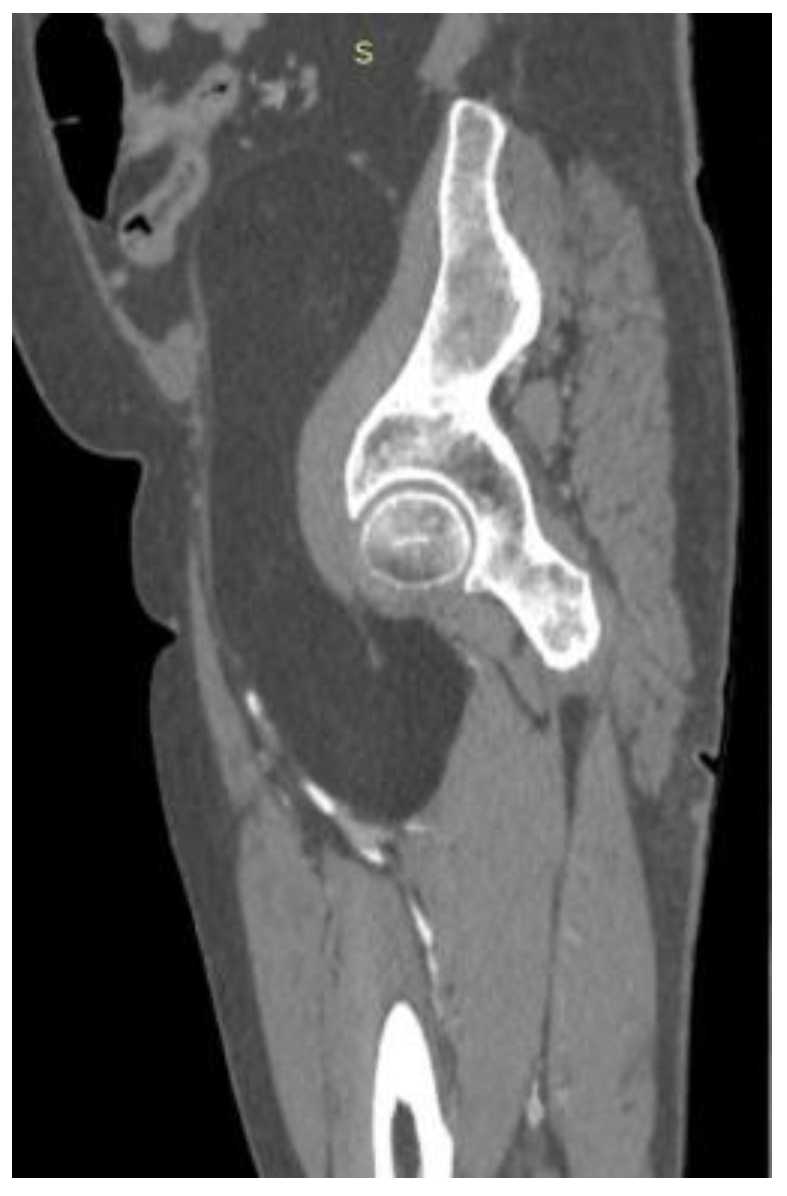

2. Case Presentation